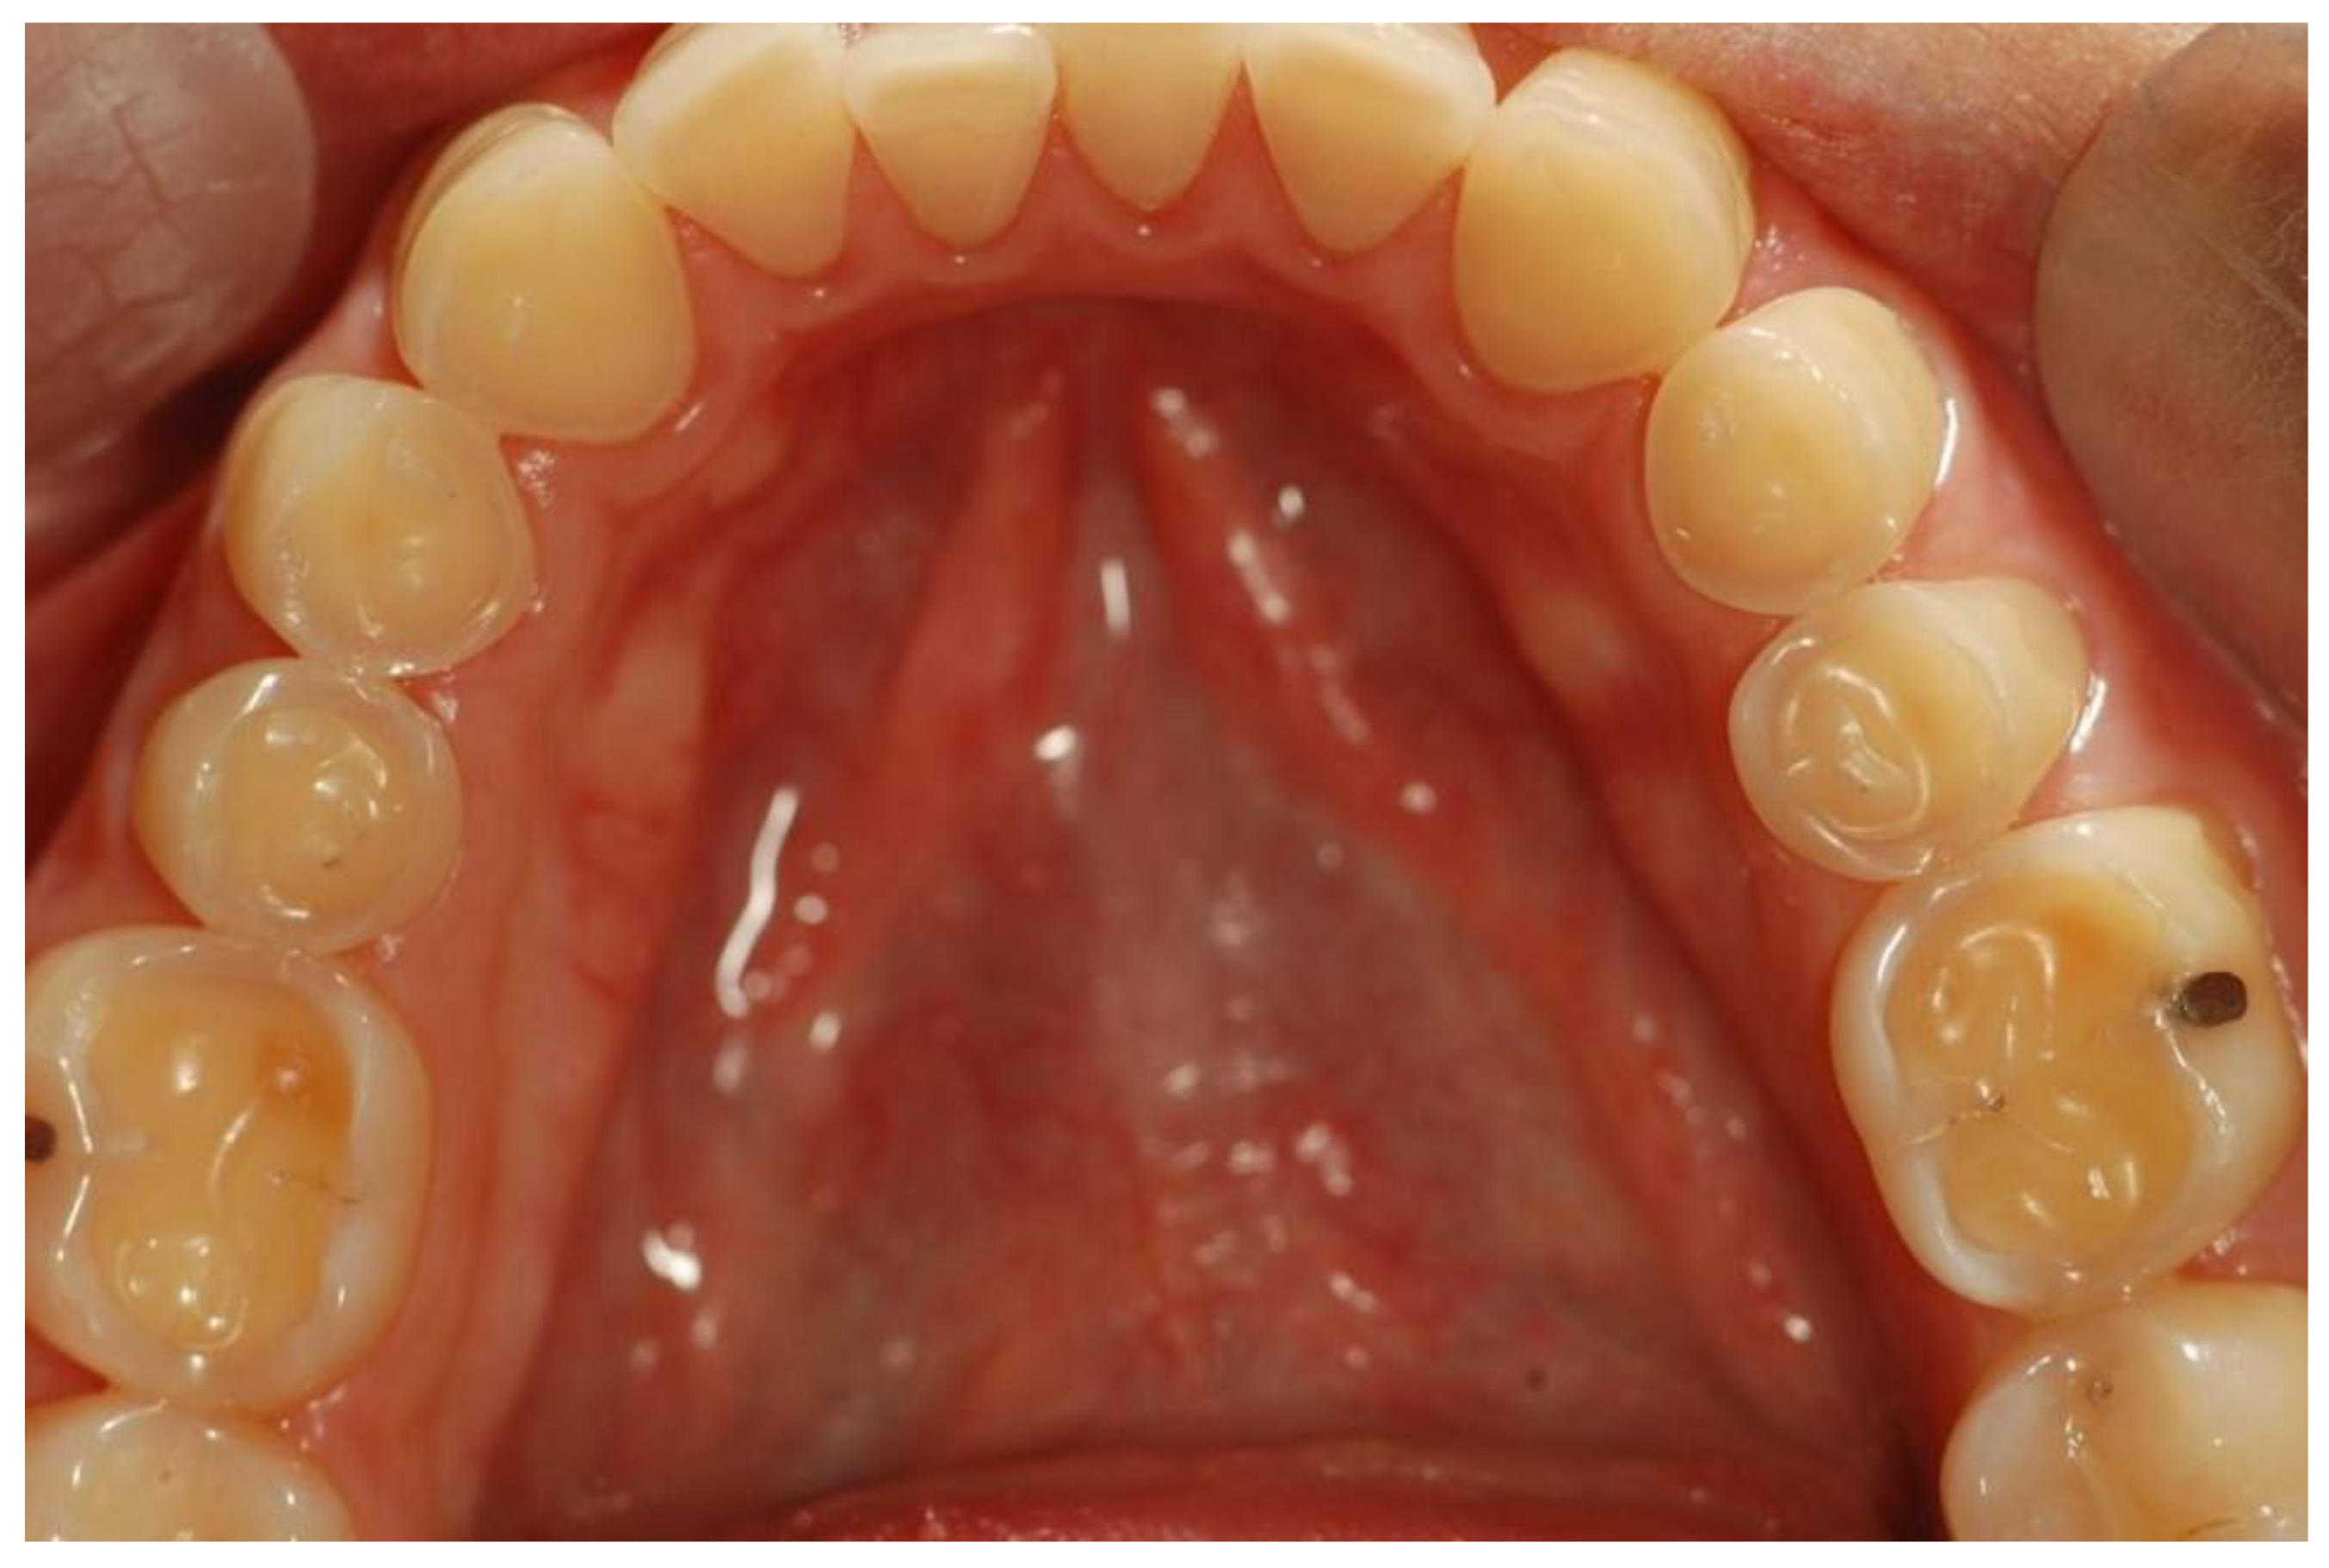

Utilizing Visual Aids for Patient Education

Visual aids are not just supplementary tools; they are crucial elements in bridging the communication gap between dentists and patients. By using diagrams, models, and digital presentations, we can demystify complex dental procedures and conditions. For instance, a 3D model of the teeth can help patients understand the intricacies of root canal therapy or the importance of proper alignment for oral health.

Moreover, incorporating visual content like informative videos can significantly enhance patient comprehension. Videos that depict proper brushing and flossing techniques or the progression of gum disease can be both captivating and educational. This dynamic approach to patient education not only informs but also engages patients in their own oral health journey.